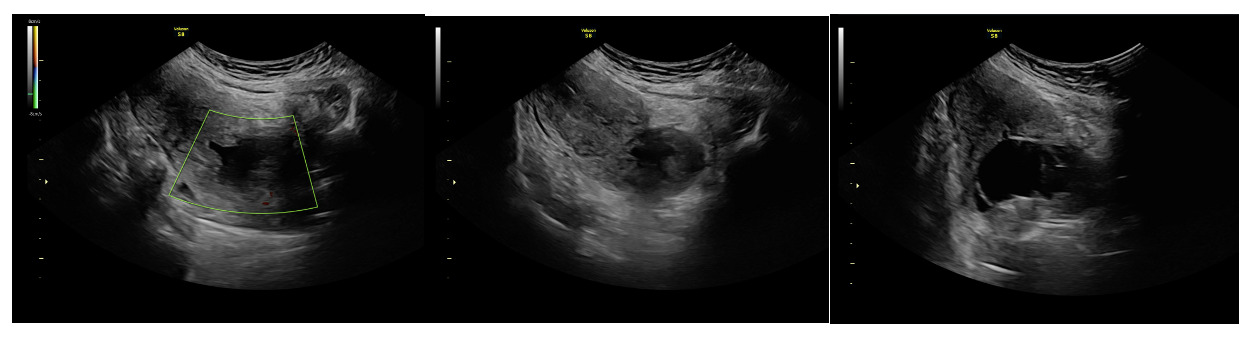

On admission for planned D&C, consents for laminaria placement, suction dilation and curettage under ultrasound guidance, possible uterine artery embolization, and possible hysterectomy were discussed and signed. The patient then underwent successful placement of a large and a medium-sized laminaria without complication. She subsequently underwent suction D&C with ultrasound guidance (Figure 3). Despite the prophylactic placement of 400 micrograms of rectal misoprostol and the administration of 20 units of Pitocin in IV fluids at the start of the case, the patient experienced significant hemorrhage during the procedure with an estimated blood loss of 1500 mL. Intraoperative findings raised concern for uterine rupture (Figure 4). A Foley balloon inflated with 30cc of saline was placed for attempted intrauterine tamponade (Figure 5), and a brisk blood loss of 500 mL immediately filled the foley catheter bag. Vaginal packing and intramuscular methergine were given as additional attempts to control the bleeding, but the patient’s hemodynamic status deteriorated intraoperatively. This necessitated volume resuscitation and transfusion of two units of packed red blood cells. An emergent exploratory laparotomy was then performed to identify the source of the bleeding to repair or perform hysterectomy. A thorough survey of the uterus, adnexa, and adjacent pelvic structures revealed no overt source of bleeding, uterine rupture, or organ invasion with the uterine and bladder serosa intact. No hemoperitoneum was found. Further inspection revealed no additional blood loss beyond the 500 mL blood loss in the foley bag. Blood loss was stabilized, and the patient became hemodynamically stable. The abdomen was closed, and the patient was transferred to interventional radiology for uterine artery embolization, which additionally controlled the hemorrhage. Following embolization, the patient was stable and extubated without issue.